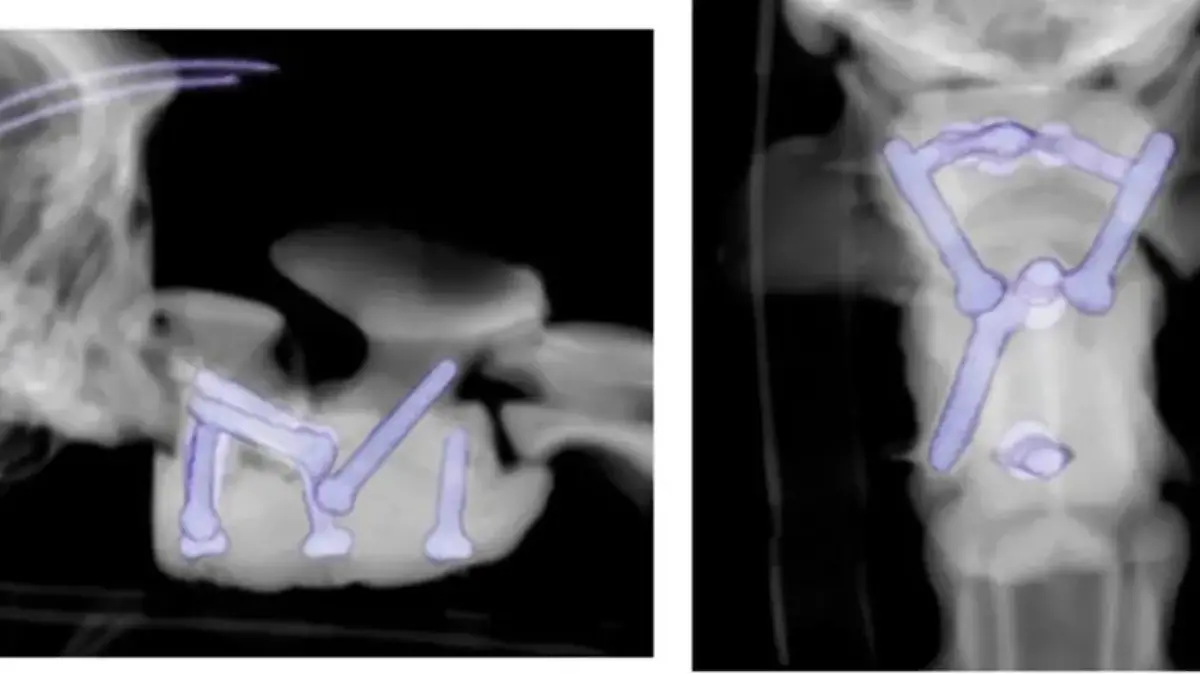

Im Chestergates Veterinary Hospital in Chester machen die Tierärzte MRT-Scans und Röntgenaufnahmen, berichtet die New York Post. Das Ergebnis: Ein Abschnitt von Arthurs Wirbelsäule ist nicht richtig miteinander verbunden. Dadurch wird das Rückenmark gequetscht, der kleine Welpe kann nicht mehr laufen.

Arthurs Rettung kommt aus dem 3D-Drucker: Die Chirurgen setzen maßgeschneiderte, 3D-gedruckte Schrauben und chirurgischen Zement in seine Wirbelsäule ein. Schon nach drei Tagen kann der Rüde schwanzwedelnd die Klinik verlassen. Jetzt – drei Monate nach der Operation – kann der kleine Cockapoo langsam wieder laufen, spielen, einfach ein ganz normaler Welpe sein. (cgo)